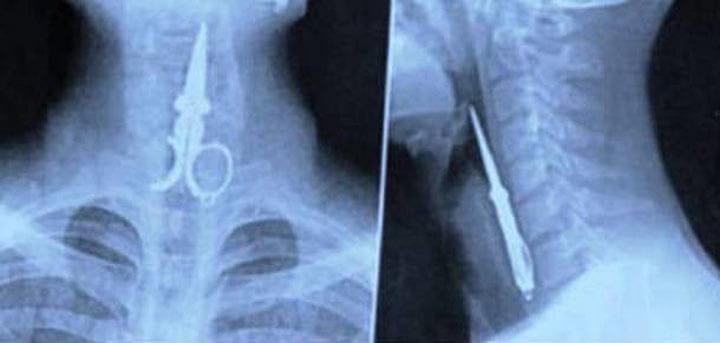

4. Маленький совет: ножницам во рту делать нечего.